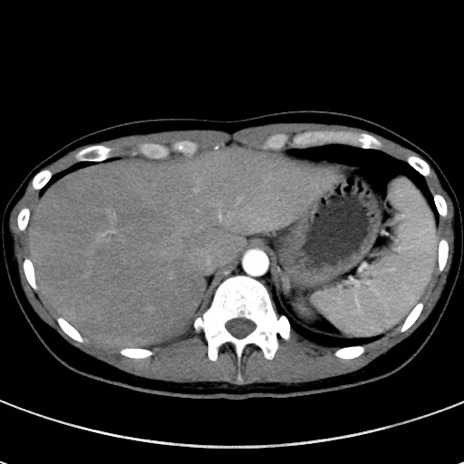

症例17(横断像)

【症例】20歳代女性

【主訴】嘔吐、下腹部痛

【現病歴】昨日夕食後に嘔吐し下腹部痛が出現。本日になっても嘔吐持続し改善しないため来院。

【身体所見】意識清明、BT 37.2℃、BP 108/67mmHg、腹部:平坦、やや硬、下腹部正中から右にかけて圧痛あり、反跳痛軽度あり、tapping pain(+)。

【データ】WBC 13600、CRP 14.94